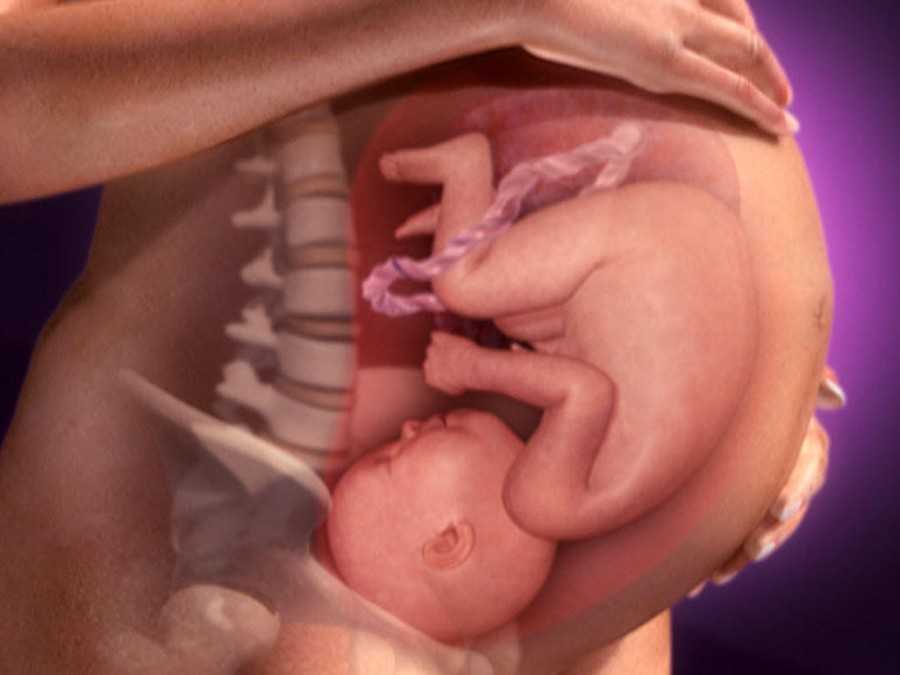

Как развивается ребенок

На 15-й неделе беременности размер плода уже хорошо увеличился, его рост составляет 10 см, а весит он примерно 50 грамм. В это время плод становится похож на человечка, он лежит, свернувшись калачиком.

У него сейчас подвижное и гибкое тело, уже сжимаются кулачки, руки в суставах сгибаются. На УЗИ видно, что он постоянно сосет палец руки. Плод обтянут очень тонкой прозрачной кожицей красноватого цвета. В это время на ней начинает появляться пушок.